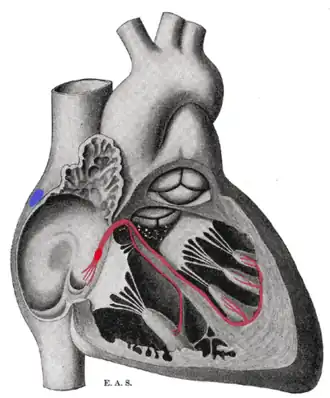

The cardiac pacemaker is the heart's natural rhythm generator. It employs pacemaker cells that produce electrical impulses, known as cardiac action potentials, which control the rate of contraction of the cardiac muscle, that is, the heart rate. In most humans, these cells are concentrated in the sinoatrial (SA) node, the primary pacemaker, which regulates the heart’s sinus rhythm.

The sinoatrial node (SA node) is the primary pacemaker of the heart. It is a region of cardiac muscle on the wall of the upper right atrium near to the superior vena cava entrance. The cells that make up the SA node are specialized cardiomyocytes known as pacemaker cells that can spontaneously generate cardiac action potentials. These signals are propagated through the heart's electrical conduction system.[1][2] Only one percent of the heart muscle cells are conductive, the rest of the cardiomyocytes are contractile.

The SA node controls the rate of contraction for the entire heart muscle because its cells have the quickest rate of spontaneous depolarization, thus they initiate action potentials most quickly. The action potential generated by the SA node passes down the electrical conduction system of the heart, and depolarizes the other potential pacemaker cells at the AV node to initiate action potentials before these other cells have had a chance to generate their own spontaneous action potential, thus they contract and propagate electrical impulses to the pace set by the cells of the SA node. This is the normal conduction of electrical activity in the heart.

The atrioventricular node and the Bundle of His, a little further down, are located in the region separating the atria from the ventricles known as the atrioventricular junction. The Bundle of His transmits signals to the bundle branches, which send them on to the Purkinje fibers. These will also produce a spontaneous cardiac action potential at a rate of 30–40 beats per minute, so if the SA and AV node both fail to function, these cells can also become pacemakers but with a much lower rate of conduction than either the primary or secondary pacemakers.